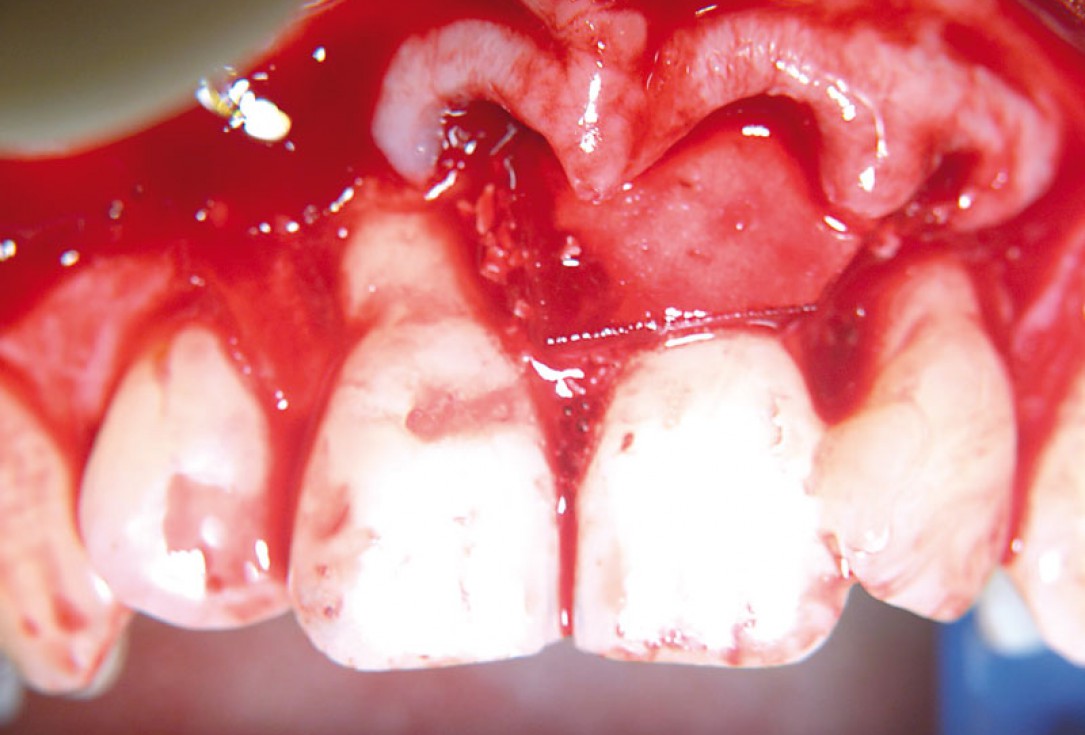

05/11 - Straumann® Emdogain® applied on the cleaned and pre-conditioned root surface.Non-contained intrabony defect treated using cerabone®, collprotect® membrane and Straumann® Emdogain® - Dr. T. Schwaar (2)